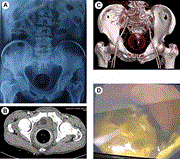

Traumatic arteriovenous fistula: a 25-year delay in presentation

Alexandra Stathis and John Gan

Journal of Surgical Case Reports, Volume 2020, Issue 3, March 2020, rjaa042, https://doi.org/10.1093/jscr/rjaa042